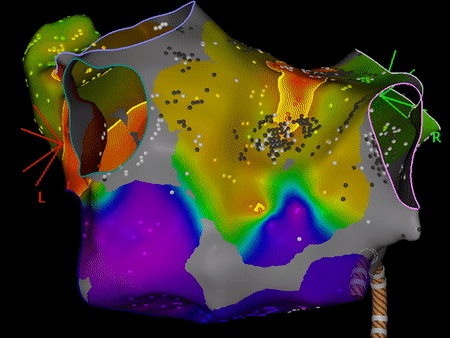

Colour inside the lines… and the left atrium! Improving step by step: segmentation Remember when you were 4 and you used to draw and paint pictures of cute animals or superheroes? Remember what your parents and your teachers used to tell you? “Colour inside the lines, do not cross the lines when you are painting!”. …